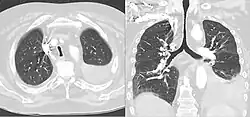

On typical CT scans of the trachea, the normal appearance is oval, round, or horseshoe shaped. A saber-sheath trachea has distinct findings compared to normal tracheas on imaging, and may have additional features on CT besides intra-thoracic narrowing and widening diameter of the posterior portion. When cartilage becomes weak, as in saber-sheath trachea, CT scans can show the sides of the trachea curving inwards. This can be more apparent with forceful exhalation Moreover, the walls of the trachea within the thorax can also show slight thickening on CT. Another finding that can be seen is the hardening and becoming more bone-like of the cartilaginous rings in the trachea, a process called ossification.[5]